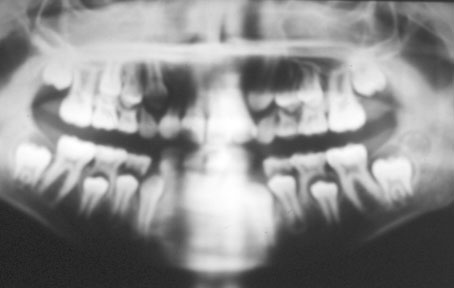

Meryème M âgée de 9 ans lors des premiers examens complémentaires (radiographies, modèles et photographies). Cette jeune patiente présente une classe II 1 Hyperdivergent, supraclusie et encombrement incisif inférieur important en denture mixte.

Radiographies avant traitement (Fig. 10, 11)